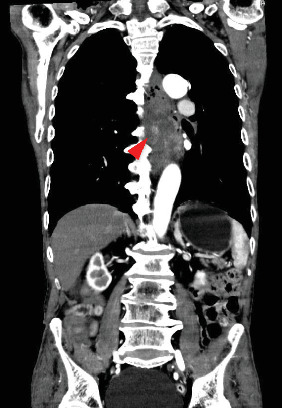

Esophageal bleeding management typically involves endoscopy but becomes challenging with large or hemorrhagic tumors, especially in cases of rare basal cell carcinoma. This malignancy, with a poorer prognosis than squamous cell carcinoma, often requires definitive surgery. A 78-year-old man with severe hematemesis underwent transarterial embolization (TAE) after failed endoscopic hemostasis for a middle thoracic esophageal tumor. Subsequently, he successfully underwent radical tumor resection on the seventh day of hospitalization. While emergency surgery is an option, its invasiveness may be a limitation, especially for patients in poor general condition. TAE is effective for hemostasis and serves as a crucial bridge to radical esophageal tumor resection.